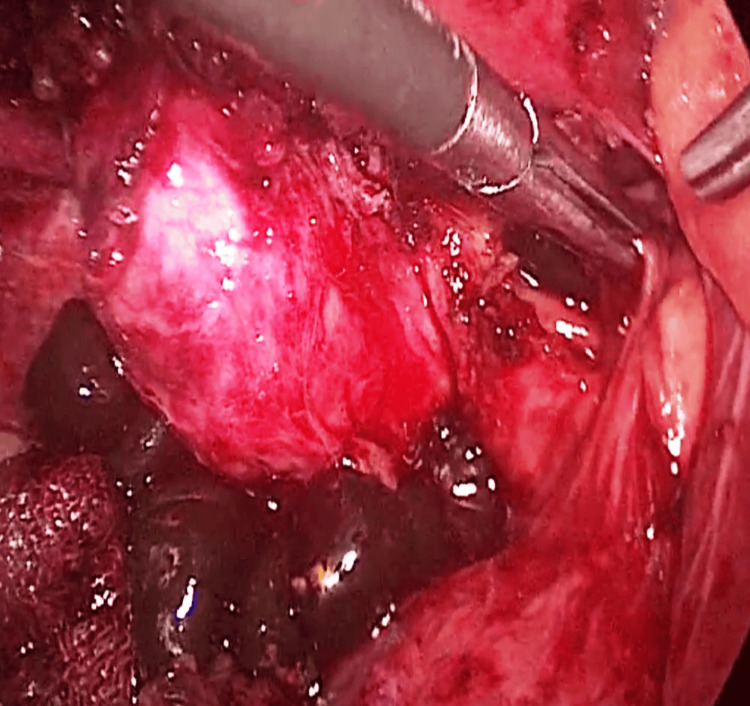

Trans-cystic LCBDE was performed in seven patients, and supra-duodenal choledochotomy was performed in the remaining 29 patients, as shown in Figure 2.

Retained stones were found in two patients undergoing trans-cystic LCBDE and were subsequently managed by supra-duodenal choledochotomy using LCBDE. Small missed stones were detected in two patients undergoing supra-duodenal choledochotomy in the LCBDE group, who were subsequently managed by ERCP.